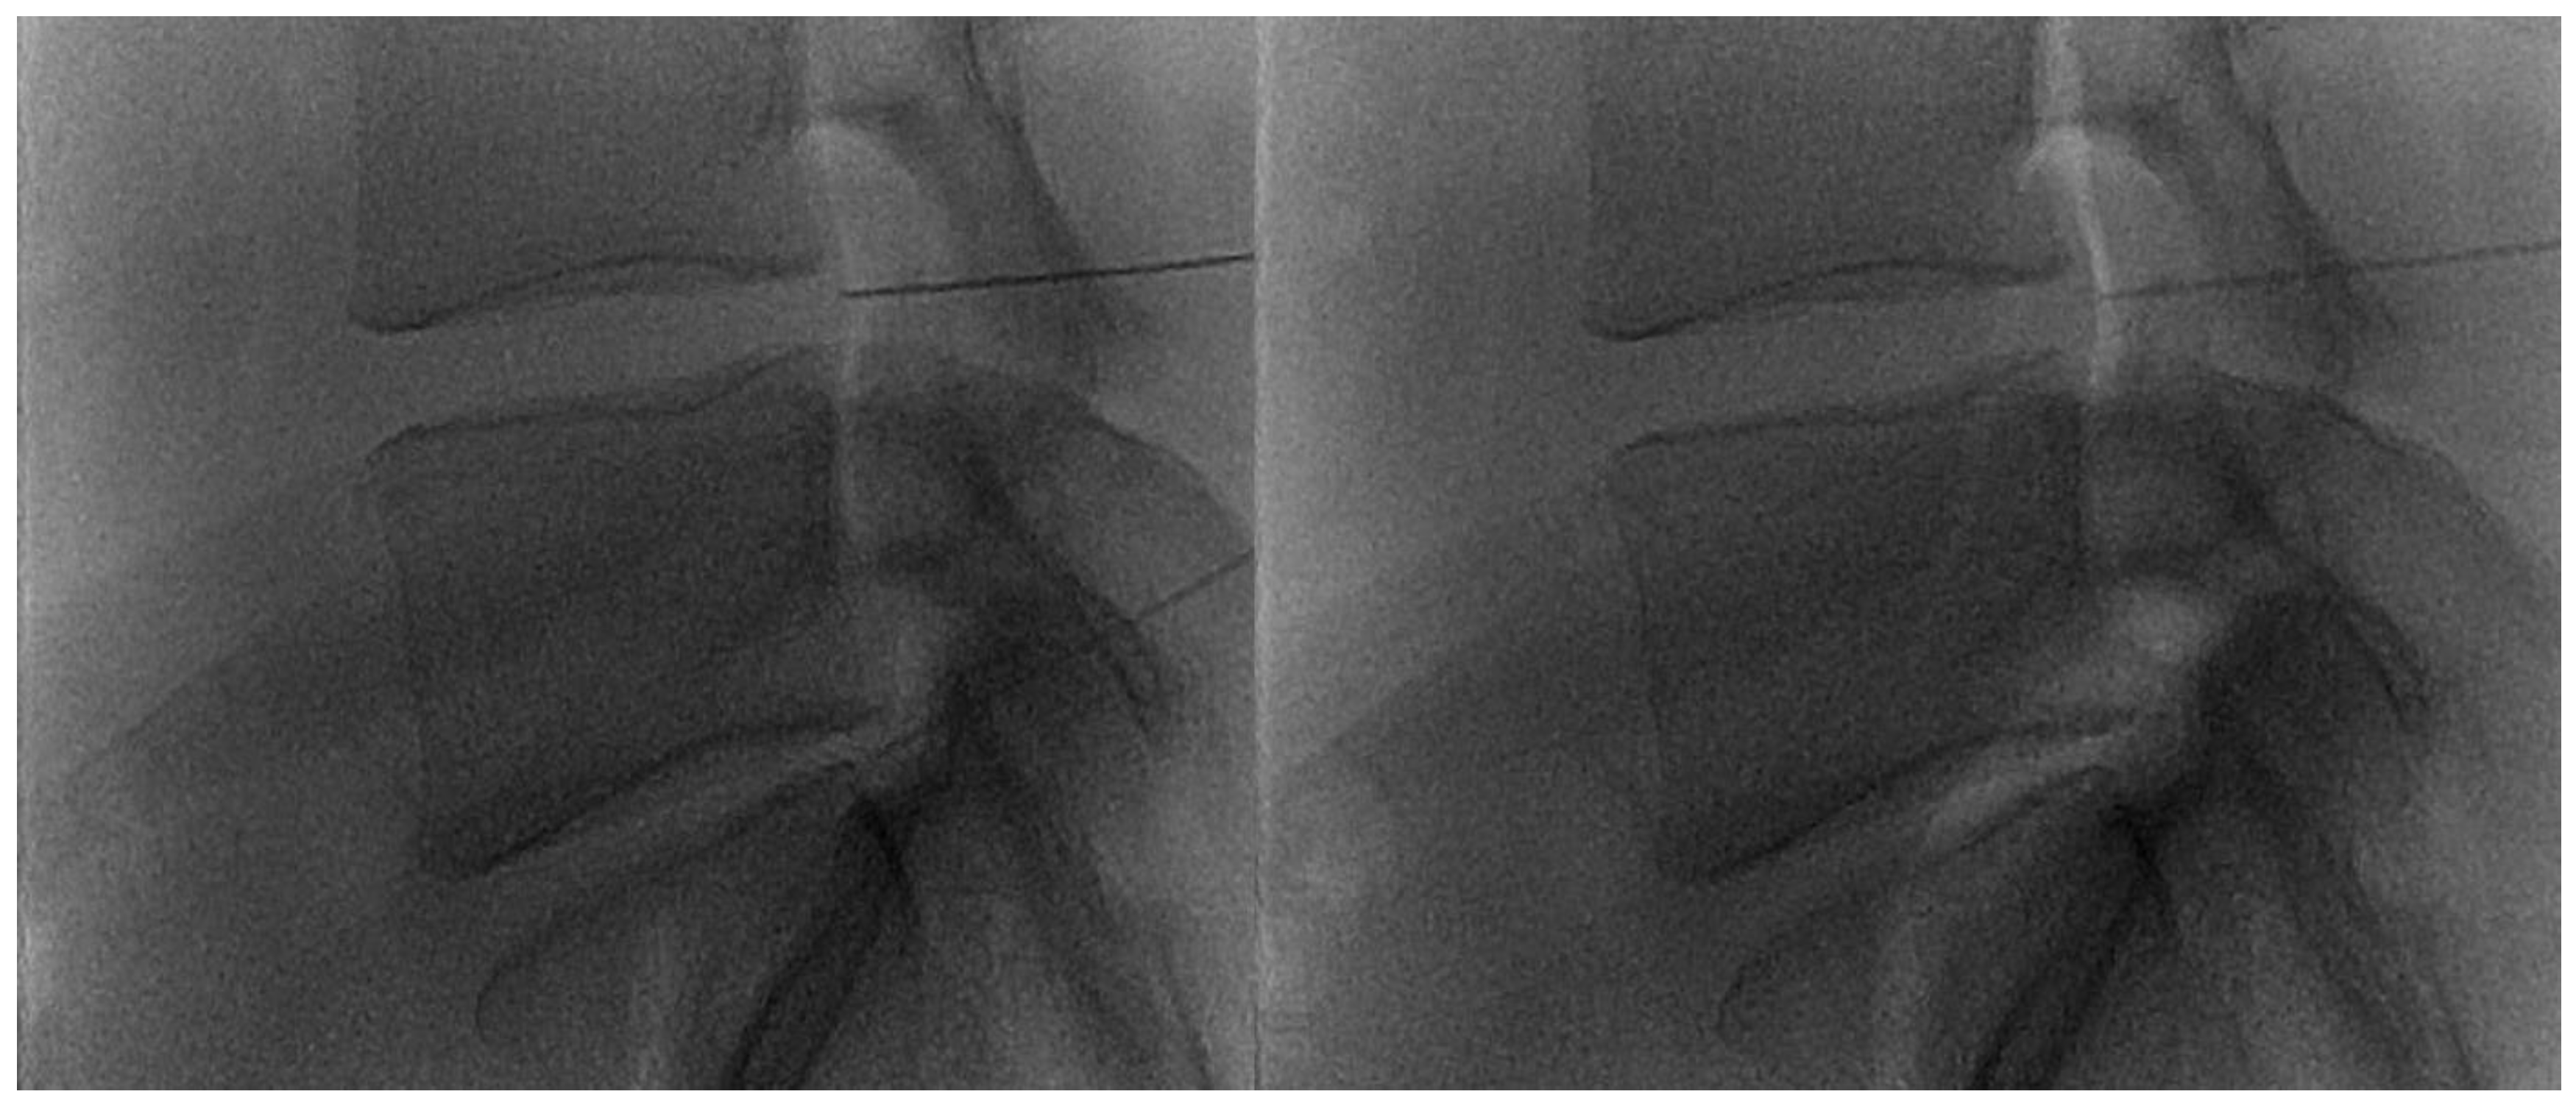

The disc center is the ideal injection target, and the prone position, employing support under the abdomen or the neck to increase the posterior vertebral space, is the optimum posture to expand the intervertebral space [48]. The access site is always selected after radiographic evaluation of the needle path; it is suggested to follow a lateral inclination of 45° to 60°, with an additional craniocaudal inclination for lumbar discs [56,57]. Some authors indicate the foramen radicularis, maintaining the root laterally and superiorly, as the best way to access the center of the disc (Figure 2 and Figure 3) [58].

Figure 2.

(A,B) Lateral and frontal view on fluoroscopic images of a lumbar intersomatic disc puncture with a 22G needle.